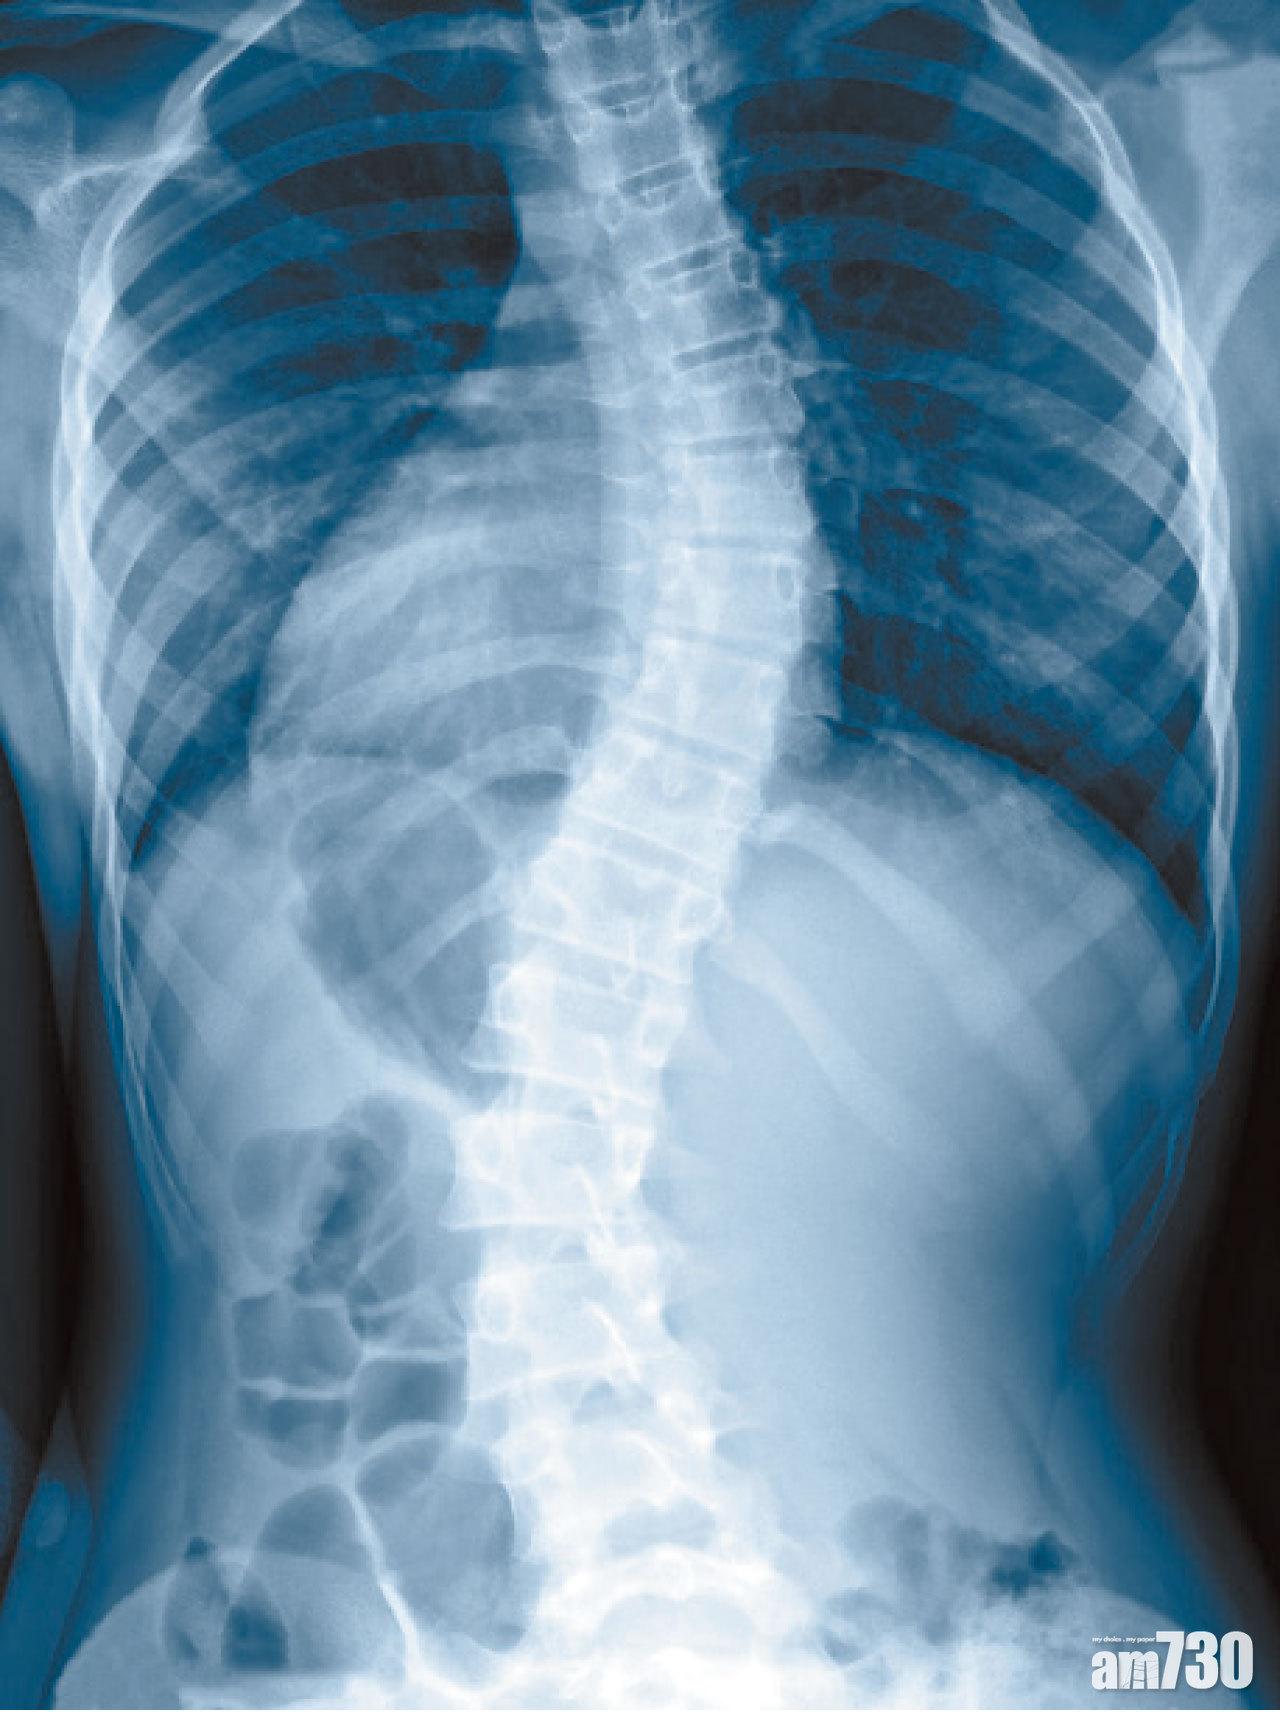

脊柱側彎(Scoliosis)影響任何年紀的人,通常於10至15歲發病,大概3%的青少年受影響。除了脊柱彎曲,患者有高低膊、坐姿不正、一邊肩膊或骨頭隆起和衣不稱身等表現,部分病人亦感背痛。大約八成患者屬原發性,相信與遺傳基因有關,跟不良姿勢和運動無關,亦不能有效預防。此病男女同受影響,可是一旦病發,女士則較嚴重。少部分屬先天性,因骨骼在母體內發育不全,亦有由肌肉或神經系統病間接導致,例如腦麻痹和肌肉萎縮病。至於長者,則較多因勞損而導致退化性脊柱側彎。雖然脊柱側彎一旦發生不會自動消失,但大部分患者情況輕微,且並不代表嚴重隱疾,因此並不需治療。脊柱側彎可隨兒童成長惡化,影響外觀、導致長期背痛,甚至胸腔變形,心肺受壓而影響功能,但此乃屬少數。